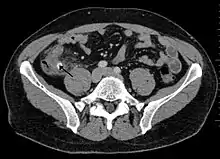

Инструментальное обследование

Ультразвуковое исследование — дилятация просвета (диаметр более 6 мм), отсутствие перистальтики, иногда может лоцироваться копролит. Ультразвуковое исследование должно быть первым инструментальным обследованием при подозрении на аппендицит. Обнаруживаются наполненная жидкостью, несжимаемая трубчатая конструкция с диаметром, превышающим 6 мм, аппендиколит, околоаппендикулярная перицекальная жидкость.

- Наиболее частый эхопризнак острого аппендицита — наличие свободной жидкости в правой подвздошной ямке (то есть, вокруг отростка) и (или) в полости малого таза (наиболее отлогом месте брюшной полости) — симптомы местного перитонита.

- Ультразвуковое исследование при остром аппендиците не всегда специфично. Для лоцирования (обнаружения) червеобразного отростка требуются: наличие обтурации отростка, опыт и аппарат экспертного класса. При гангренозно-перфоративном аппендиците, содержимое отростка изливается в брюшную полость, дилятация исчезает, отросток может не лоцироваться. Вместе с тем, обязательно лоцируется свободная жидкость в брюшной полости, может лоцироваться «свободный газ» в брюшной полости, паретичные петли тонкой кишки.

Усложняют ультразвуковое исследование кишечные газы, ожирение, защитная фиксация, движения. Обнаружение нормального аппендикса при ультразвуковом исследовании является основанием для исключения аппендицита.

Компьютерная томография информативна при наличии спирального томографа, когда выявляется обтурация червеобразного отростка, расширение его просвета, утолщение стенки (> 1 мм) признаки свободной жидкости (воспалительного выпота) в брюшной полости.